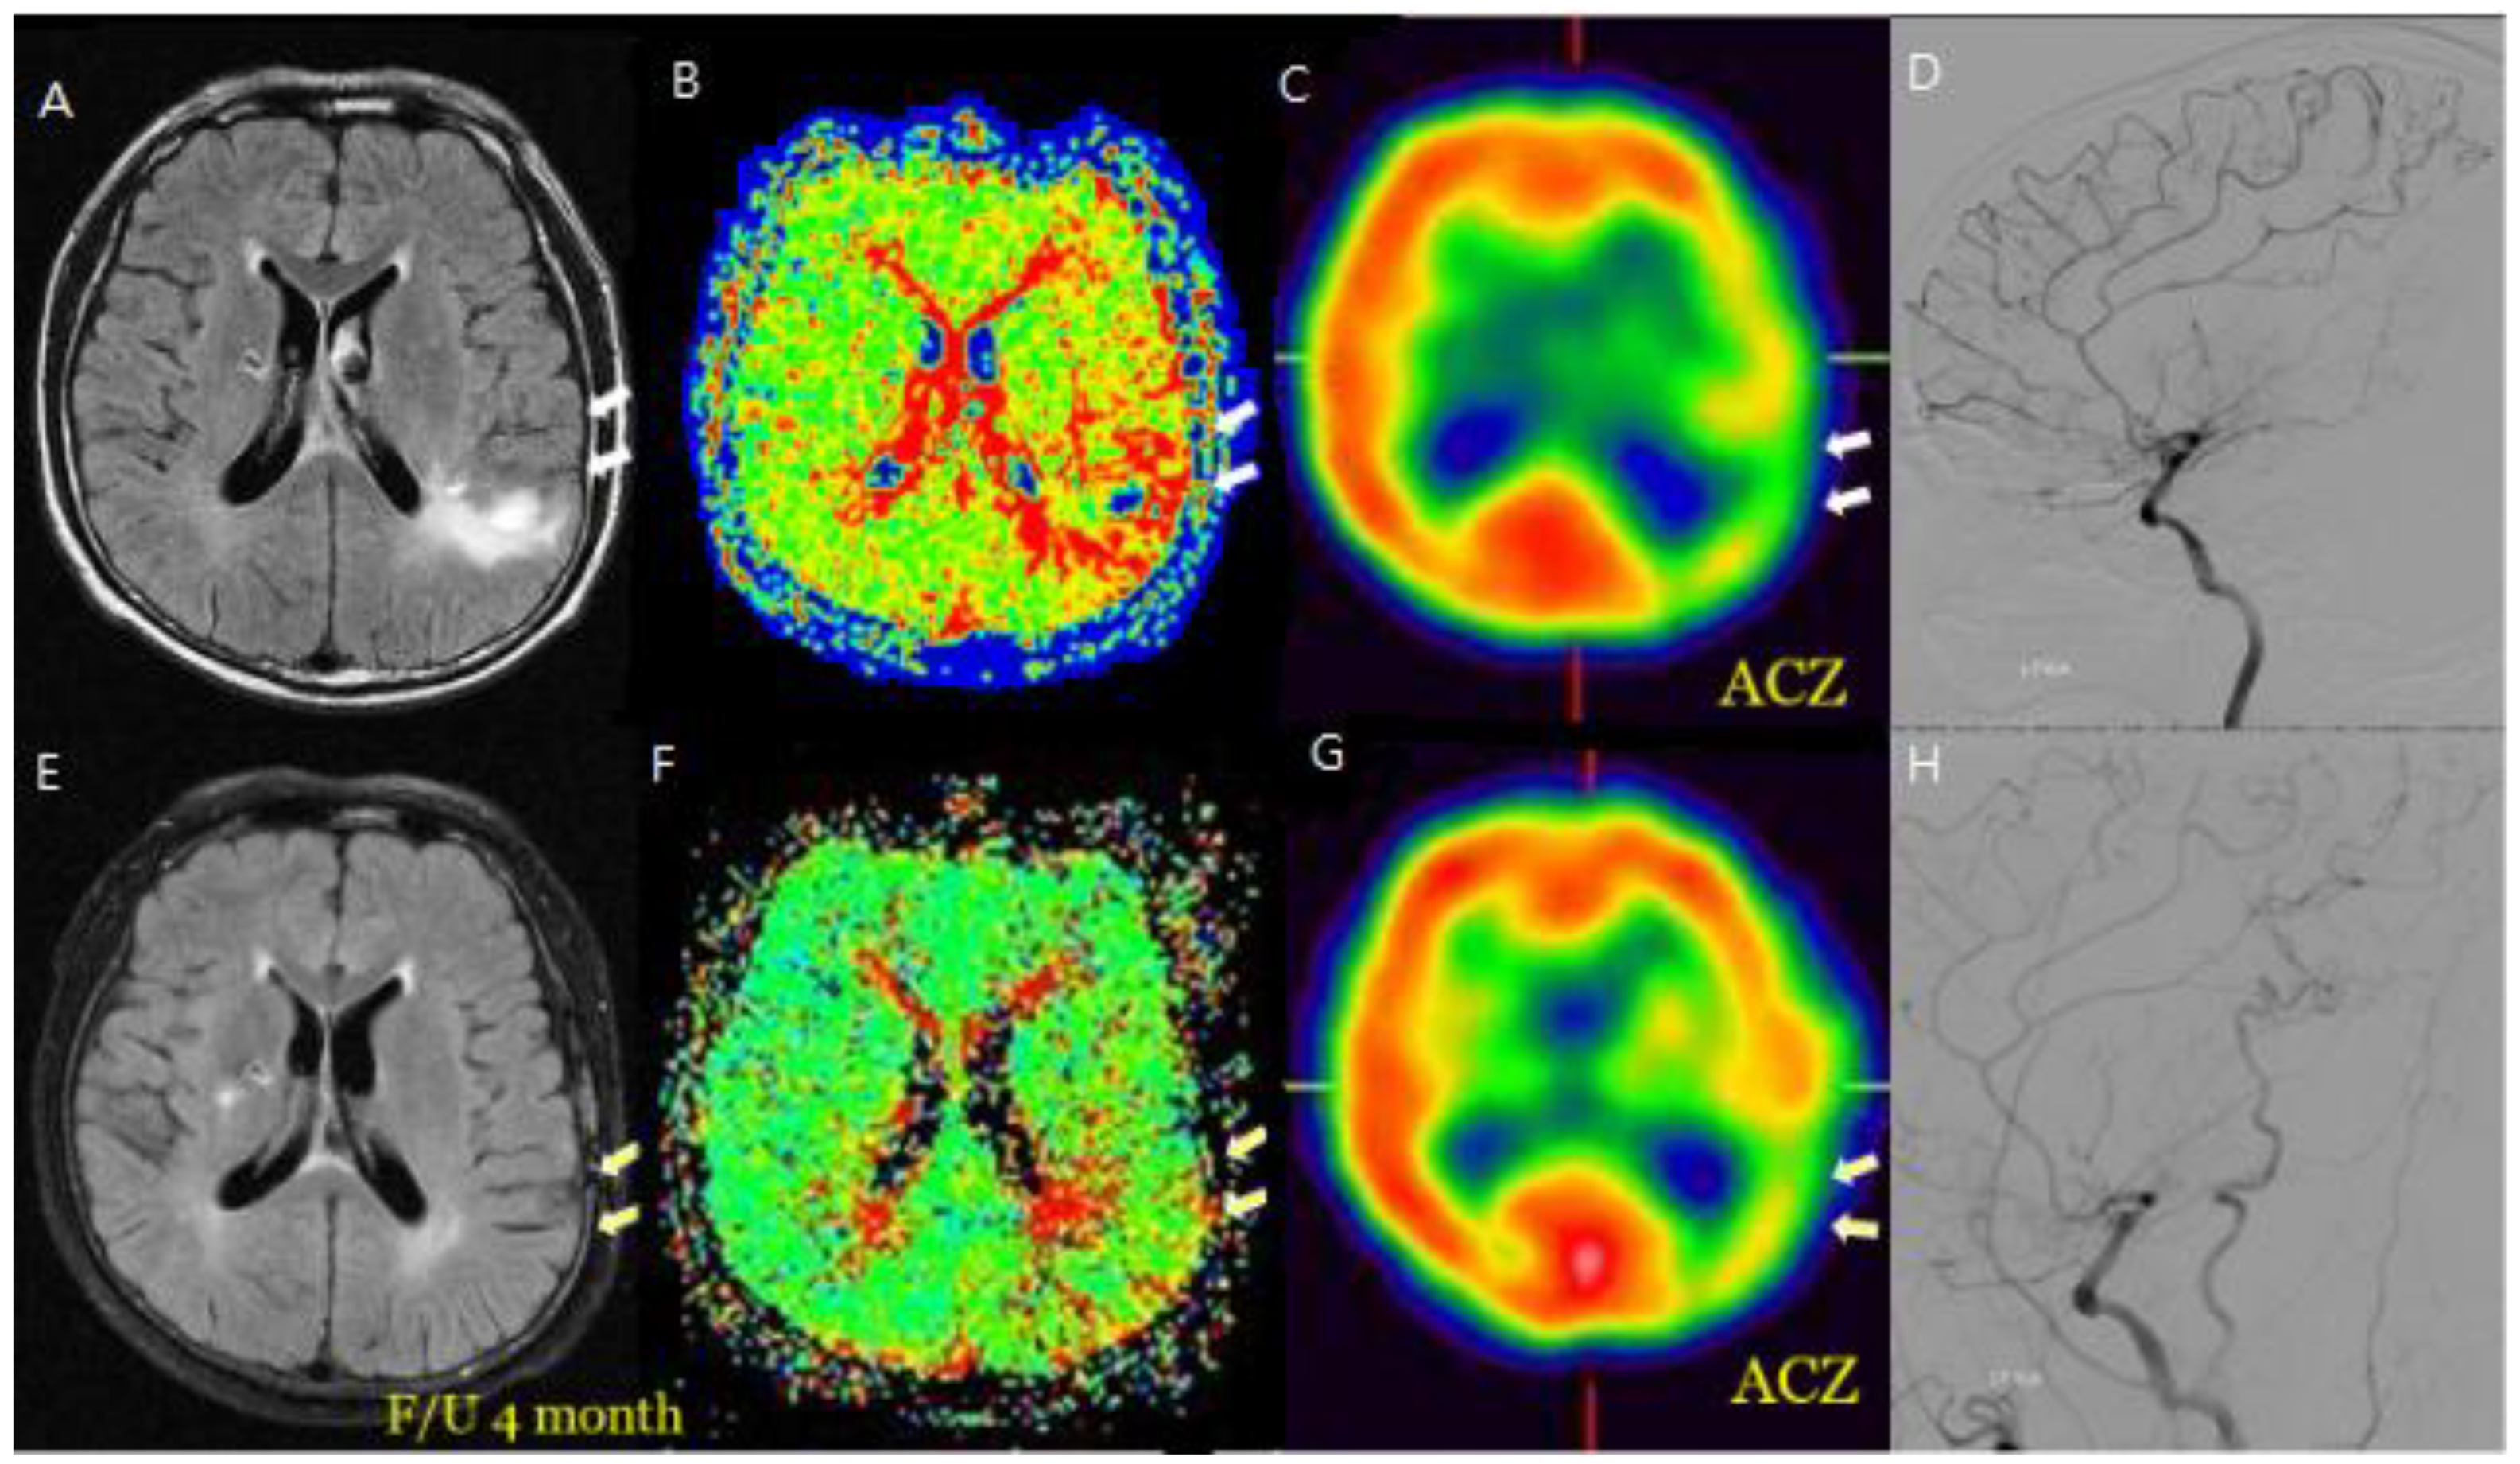

Figure 2. M/58 symptomatic steno-occlusive patient (Rt. Hemiparesis with Lt. M1 occlusion). Preoperative MR FLIAR and Perfusion MR, SPECT (A, B, C, D) shows Hyperintense vessels indicated decreased cerebral vascular reserve and postoperative decrease or disappeared hyperintense vessels were revealed revascularization effective for decreasing HV after F/U and decrease of HV on bypass-established hemisphere associated with improved hemodynamic status (E, F, G, H).

Figure 3. F/66 Lt. distal ICA severe stenosis patient. Hyperintense vessels were observed in areas with reduced blood flow and reserve before surgery (A, B, C, D), and it was confirmed that the hyperintense vessels had disappeared on the FLAIR scan after the hemodynamic condition improved following STA-MCA bypass surgery (E, F, G, H).

Additionally, changes in the ivy sign on MR FLAIR images were compared with MR perfusion images. The degree of change in mean transit time (MTT) was greater in areas with positive or minimal HV compared to areas with negative HV. After STA-MCA bypass surgery, regions where HV decreased or disappeared showed improved hemodynamics, as reflected in both SPECTand MR perfusion imaging (Figure 2).